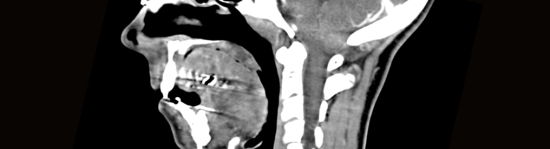

Эктопия миндалины мозжечка: признаки, диагностика и лечение 19 .01 .2021 21:44 Мозжечок - часть головного мозга, отвечающая за координацию движений, мышечный тонус, регулирующая настроение .

Симптомы заболевания . Опущение миндалины мозжечка в большое затылочное отверстие иногда не проявляется клинически и регистрируется случайным образом в процессе томографии .

Симптомы эктопии миндалин мозжечка сложно определить клиническим методом . Но порой вероятно проявления неврологического характера - болевые ощущения в области шеи во время нагрузок либо мышечного напряжения .

Симптомы заболевания Эктопия миндалин мозжечка проявляется разными симптомами, которые будут зависеть от разновидностей аномалии Арнольда Киари . Нейрохирург либо невролог способны точно определить тип заболевания . Зачастую в клинической практике нейрохирургов обнаруживается мальформация Арнольда Киари 1 степени .